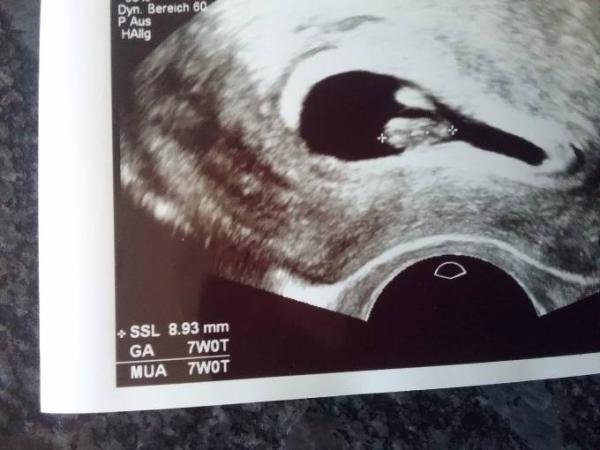

War heute beim Arzt. Herzchen bubbert und unser Baby ist jetzt 9mm gross.

Hat sich alles gut entwickelt